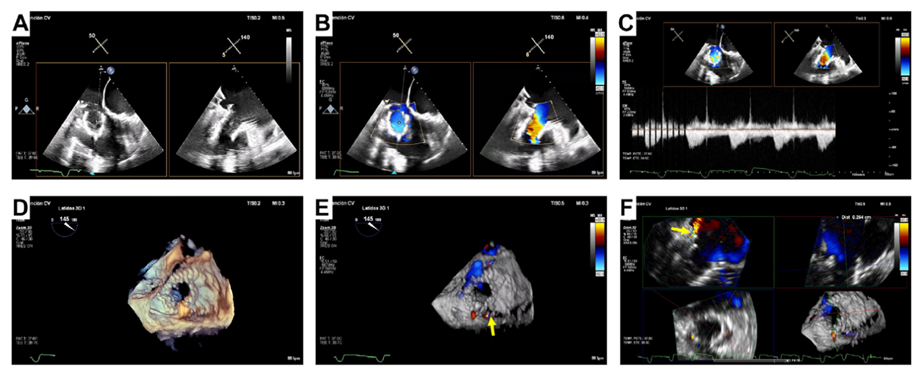

基線經(jīng)胸和經(jīng)食道超聲

術(shù)后經(jīng)食道超聲,僅微量瓣周漏